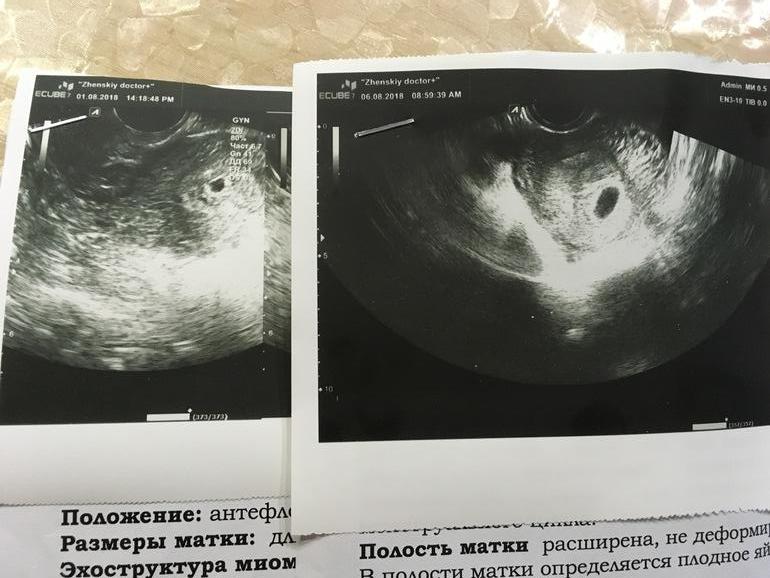

Это первое и через неделю второе Узи

Ну хорошо же. Растет. Девочки пишут что раньше 7 недель у многих не находят эмбриона и сб.

Было 5 мм стало 13 мм